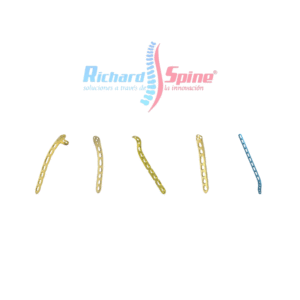

Placa Epifisaria

- La Placa epifisaria es utilizada para la corrección de deformidades pediátricas.